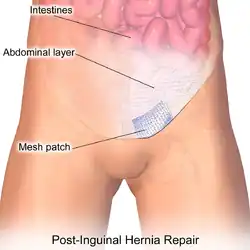

Open hernia repair

All techniques involve an approximate 10-cm incision in the groin. Once exposed, the hernia sac is returned to the abdominal cavity or excised and the abdominal wall is very often reinforced with mesh.[11] There are many techniques that do not utilize mesh and have their own situations where they are preferable.[25][17]

Open repairs are classified via whether prosthetic mesh is utilized or whether the patient's own tissue is used to repair the weakness. Prosthetic repairs enable surgeons to repair a hernia without causing undue tension in the surrounding tissues while reinforcing the abdominal wall. Repairs with undue tension have been shown to increase the likelihood that the hernia will recur. Repairs not using prosthetic mesh are preferable options in patients with an above-average risk of infection such as cases where the bowel has become strangulated (blood supply lost due to constriction).[21]

Open mesh repairs

Repairs that utilize mesh are usually the first recommendation for the vast majority of patients including those that undergo laparoscopic repair.[12] Procedures that employ mesh are the most commonly performed as they have been able to demonstrate better results compared to non-mesh repairs.[21] Approaches utilizing mesh have been able to demonstrate faster return to usual activity, lower rates of persistent pain, shorter hospital stays, and a lower likelihood that the hernia will recur.[29][12][30][31][32][33]

Options for mesh include either synthetic or biologic. Synthetic mesh provides the option of using "heavyweight" as well as "lightweight" variations according to the diameter and number of mesh fibers.[34] Lightweight mesh has been shown to have fewer complications related to the mesh itself than its heavyweight counterparts.[35] It was additionally correlated with lower rates of chronic pain while sharing the same rates of hernia recurrence as compared to heavyweight options.[36][37][38] This has led to the adoption of lightweight mesh for minimizing the chance of chronic pain after surgery.[21] Biologic mesh is indicated in cases where the risk of infection is a major concern such as cases in which the bowel has become strangulated. They tend to have lower tensile strength than their synthetic counterparts lending them to higher rates of mesh rupture.[39]